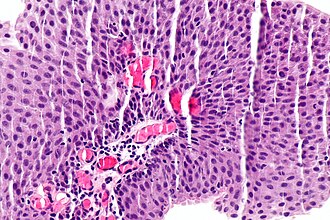

Low-grade papillary urothelial carcinoma. H&E stain. | |

| LM | papillae (fibrovascular cores covered by urothelium) -- usually with fusion and branching, small nuclei (~3x a resting lymphocyte), +/-invasion into the lamina propria (rare), +/-mitoses (uncommon) |

- Papillae = fibrovascular cores covered by urothelium.

- Usually with fusion of papillae and branching of papillae.

- Small nuclei (~3x a resting lymphocyte).

- +/-Invasion into the lamina propria (rare).

- Rare mitoses.